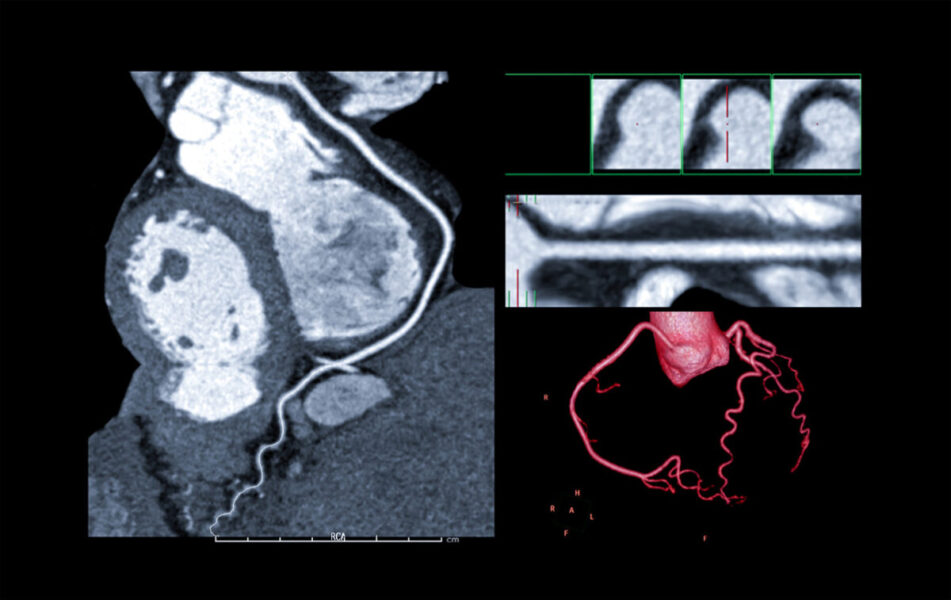

Beyond the Calcium Score: Why Cardiac CT is Now a First-Line Tool for the Modern Cardiologist Colleagues, For years, many

Coronary Artery Disease (CAD) If you live in Michigan and have been feeling unexplained chest discomfort, shortness of breath, or